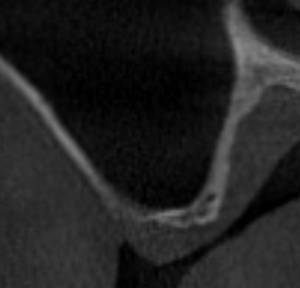

前歯の詰め物(レジン)の見た目の改善を希望されて来院。セラミック治療をすすめられたが、費用が高いのと、これ以上歯を削りたくないと言うご要望にお応え。

保険診療でのレジン修復で治療。

初診時 レジン治療終了時